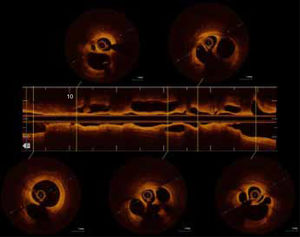

Se presenta el caso de un varón de 59 años, fumador, con antecedentes de hipertensión, diabetes y lesión de 2 vasos (arteria descendente anterior izquierda y arteria circunfleja) tratada con un injerto coronario en 2012. El paciente fue remitido a nuestro hospital con un infarto de miocardio sin elevación del segmento ST. La angiografía reveló unos injertos permeables y una luz con múltiples giros en el segmento medio de la arteria coronaria derecha (), lo cual se confirmó en la tomografía de coherencia óptica (figura 1, ). Un índice diastólico instantáneo sin ondas (iFR) de 0,73, que indica deterioro del flujo (figura 2) motivó el implante de un stent farmacoactivo, con buenos resultados (). El iFR tras el implante del stent fue de 0,98.

La evaluación fisiológica de la lesión resulta útil para el pronóstico en la revascularización percutánea, y tanto la guía europea como la estadounidense recomiendan esta práctica. Anteriormente se proponía un tratamiento conservador para la enfermedad de la arteria coronaria en entramado, pero en nuestro caso se muestra por primera vez un deterioro del flujo inducido por los microconductos en entramado. Nuestras observaciones contribuyen a mejorar el conocimiento de esta anomalía, con importantes consecuencias para el tratamiento. Esta figura se muestra a todo color solo en la versión electrónica del artículo.